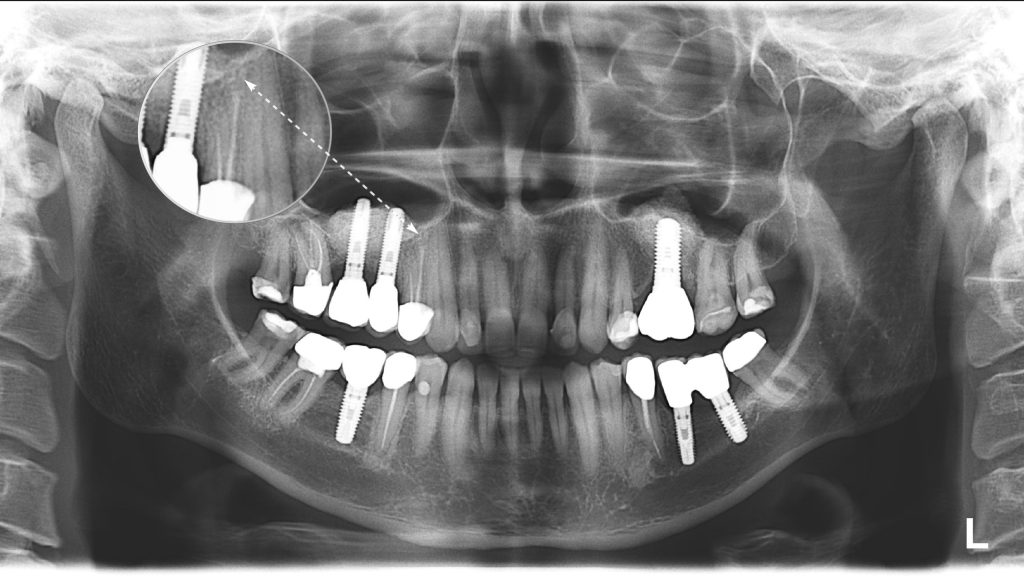

Фотографии и схемы для ОПТГ и мезиального прикуса